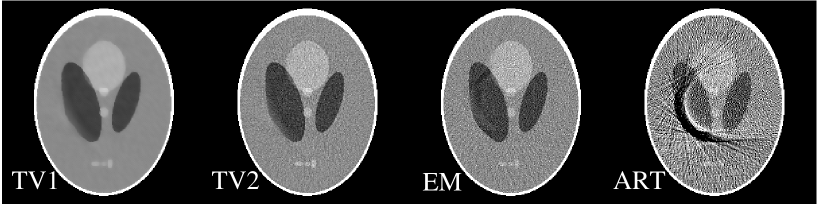

We also reexamined image reconstruction from data containing bad-bins of Sec. III.3 with the low amplitude wavy background added to the original image. In this case, the number of projection data is 58,430, which is not twice the number of non-zero pixels in the image but it is a comparable number. We display in Fig. 12 images reconstructed by use of the TV, EM, and ART algorithms. It can be observed that the TV image is visually indistinguishable from the true image. We also note that, as before, the ART and EM reconstructions are close to the original image in this case. The number of iterations for the TV algorithm is 100, which is much less than the 10,000 iterations used for both EM and ART algorithms.

For the bad bin case, we generated noisy data by adding Gaussian noise, at the level of 0.1% of the individual true data values, to the noiseless data described in Sec. III.3. In Fig. 14, we show images reconstructed by use of the TV algorithm (TV1) and (TV2), the EM, and the ART algorithm. The iteration numbers for the TV, EM, and ART images are 200, 200, and 100, respectively. Again, we show two TV images in Fig. 13: TV1 and TV2. The results of this study suggests that the TV and EM algorithms can still effectively correct for the effect of the missing detector bins. The ART algorithm, which showed very mild streaking in Fig. 9 under the ideal condition, displays significant streaking due to the combination of signal noise and bad detector bins.